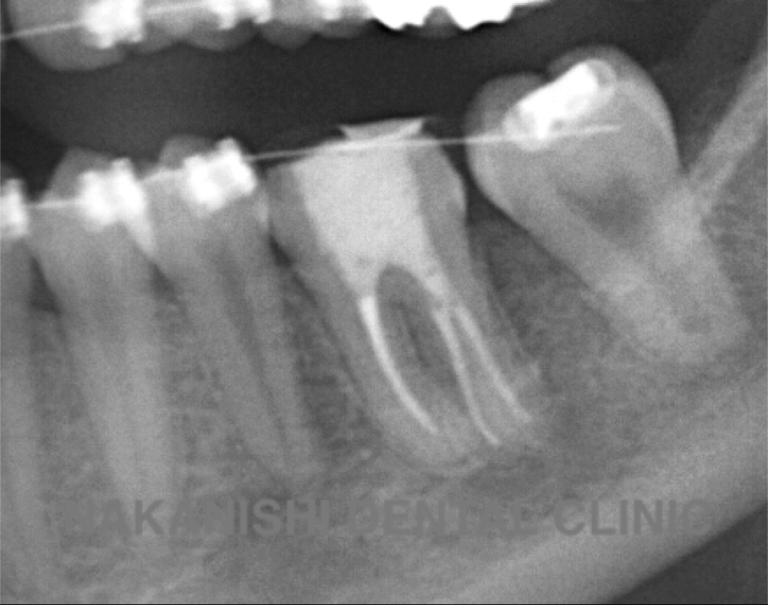

治療前

治療後

| 主訴 | 右下奥歯が痛い。 他院で『膿の袋が大きいため抜歯』と言われセカンドオピニオン希望でご来院。 |

|---|---|

| 治療期間 | 約半年(6か月) |

| 治療費 | 約5万円 |

| 治療内容 | ラバーダム、マイクロスコープ下にて根管治療を実施し、歯根端切除を行う。歯茎の腫れは消失し違和感や痛みも消失した。 |

| 治療のリスク | マイクロスコープやCTを使用し、可能な限り精密な根管治療を行っていますが、歯根の形態や病変の大きさ、過去の治療履歴などにより、治癒が得られない場合があります。 また、治療後に再感染や歯根破折が生じることもあり、その場合は再治療や抜歯が必要となることがあります。 治療結果には個人差があり、すべての症例で同様の経過を保証するものではありません。 |